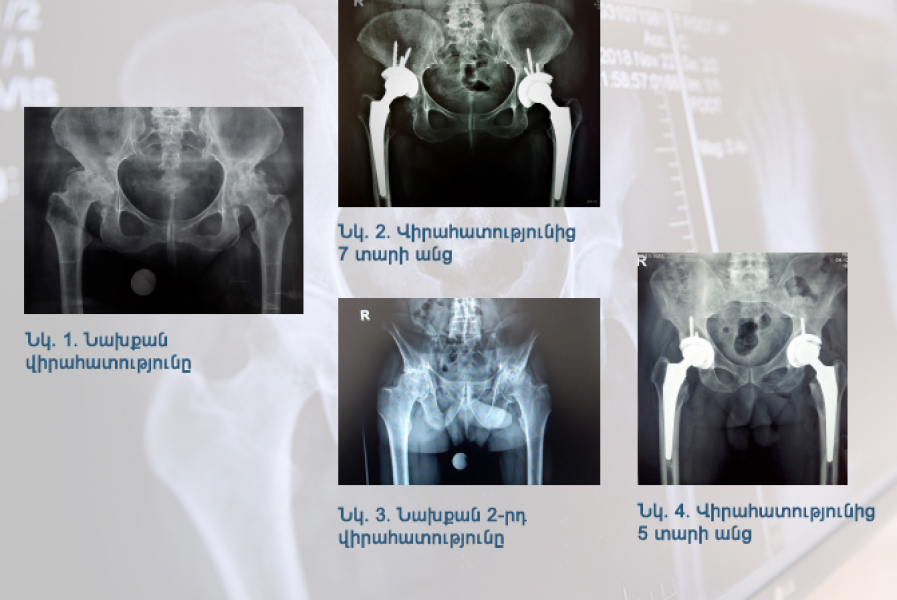

Կլինիկական դեպք. երկկողմանի անգիլիզացնող կոքսարթրոզ

«Նաիրի» բժշկական կենտրոն էր դիմել 1951 թ. ծնված տղամարդ՝ երկկողմանի անգիլիզացնող կոքսարթրոզով, առաջին աստիճանի ճարպակալումով․․․

12 Ապրիլ 2022 | Օրթոպեդիա և վնասվածքաբանություն, «Կոքսա» կլինիկա | Հրաչյա Գևորգի Հարությունյան